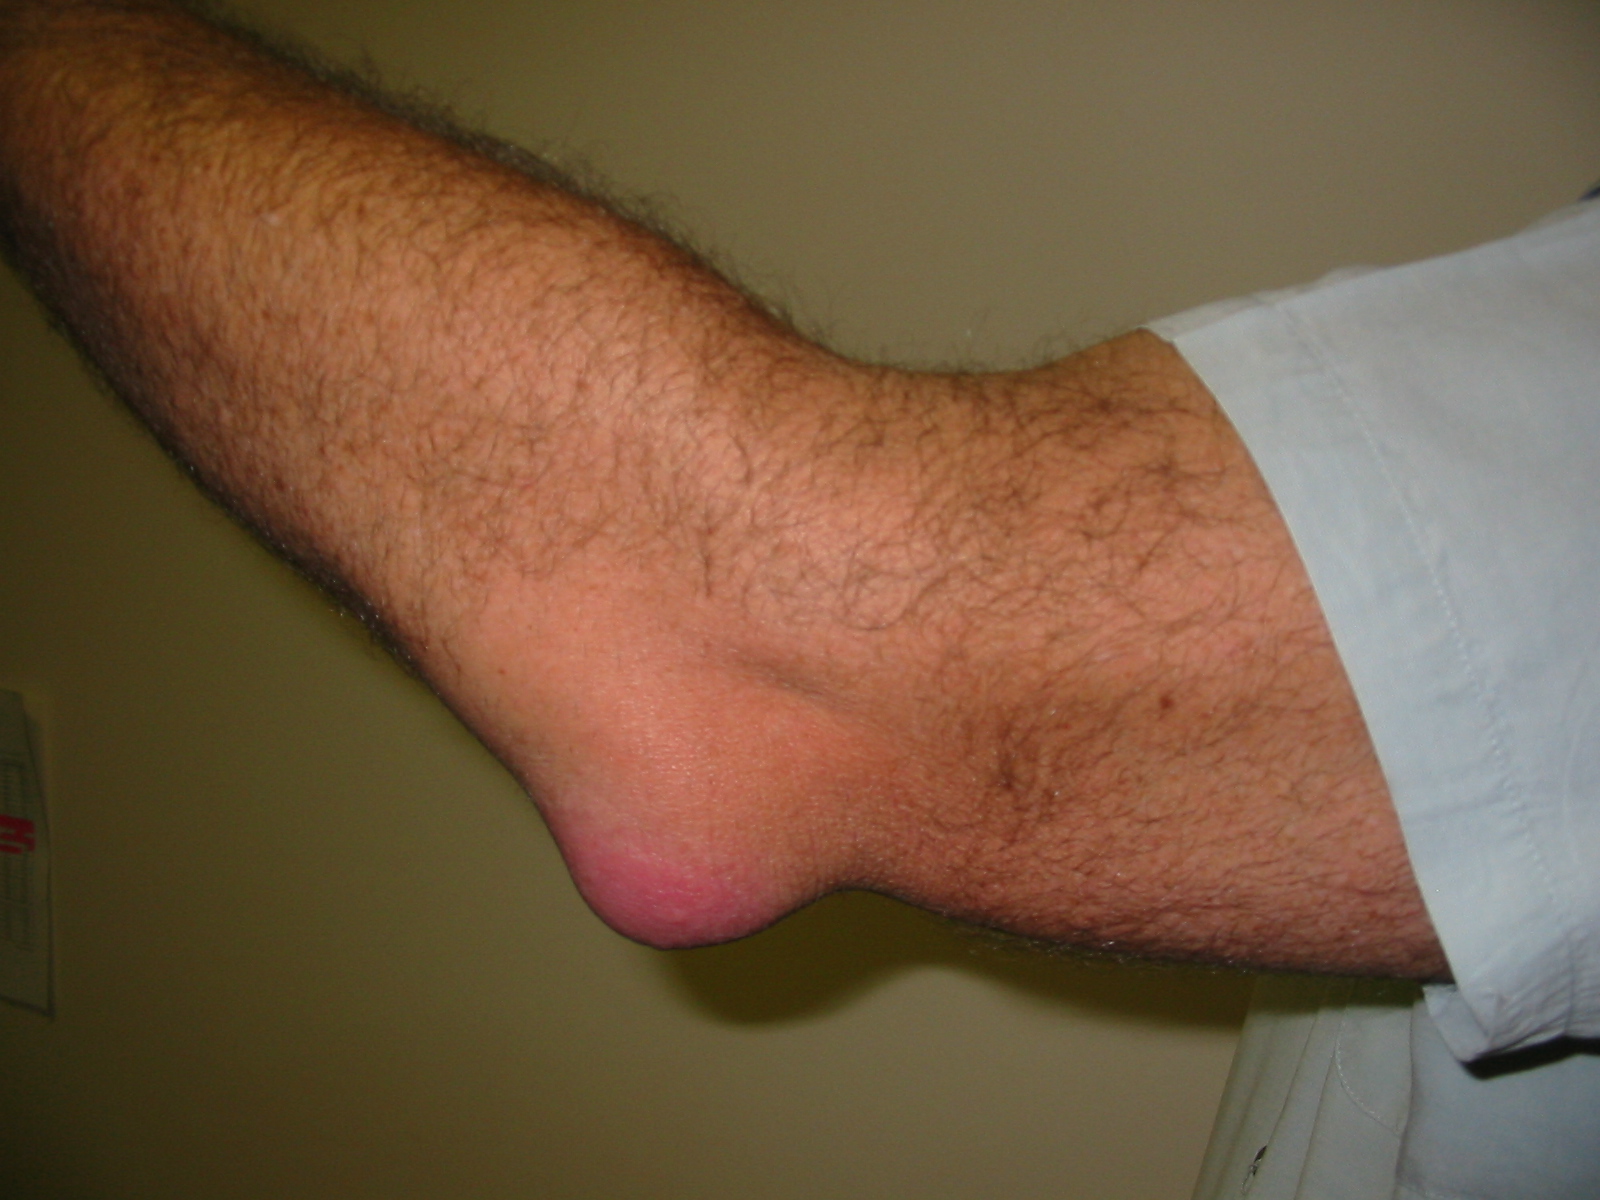

Bursitis olecraneana

¿Qué es la bursitis olecraneana (Codo de estudiante)?

Inflamación de la bolsa olecraneana subcutánea (entre piel y olécranon)

"Codo de estudiante" / "codo de minero"

Causa: apoyo prolongado sobre codo, trauma repetitivo, gota, infección

Presentación: tumefacción fluctuante en punta del codo, dolor variable

El codo mantiene movilidad completa (la bolsa es extraarticular)

Tratamiento: evitar apoyo, aspiración si tensa, antibióticos si infectada